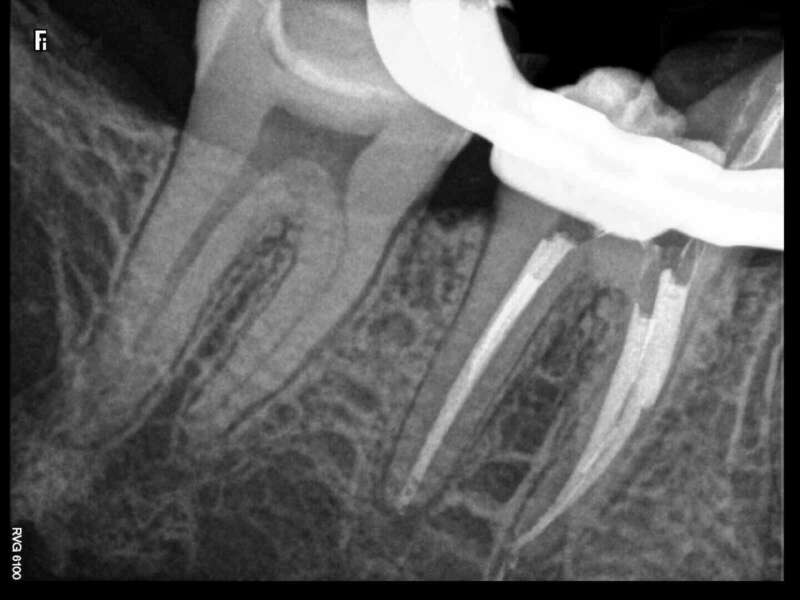

Avant

Après